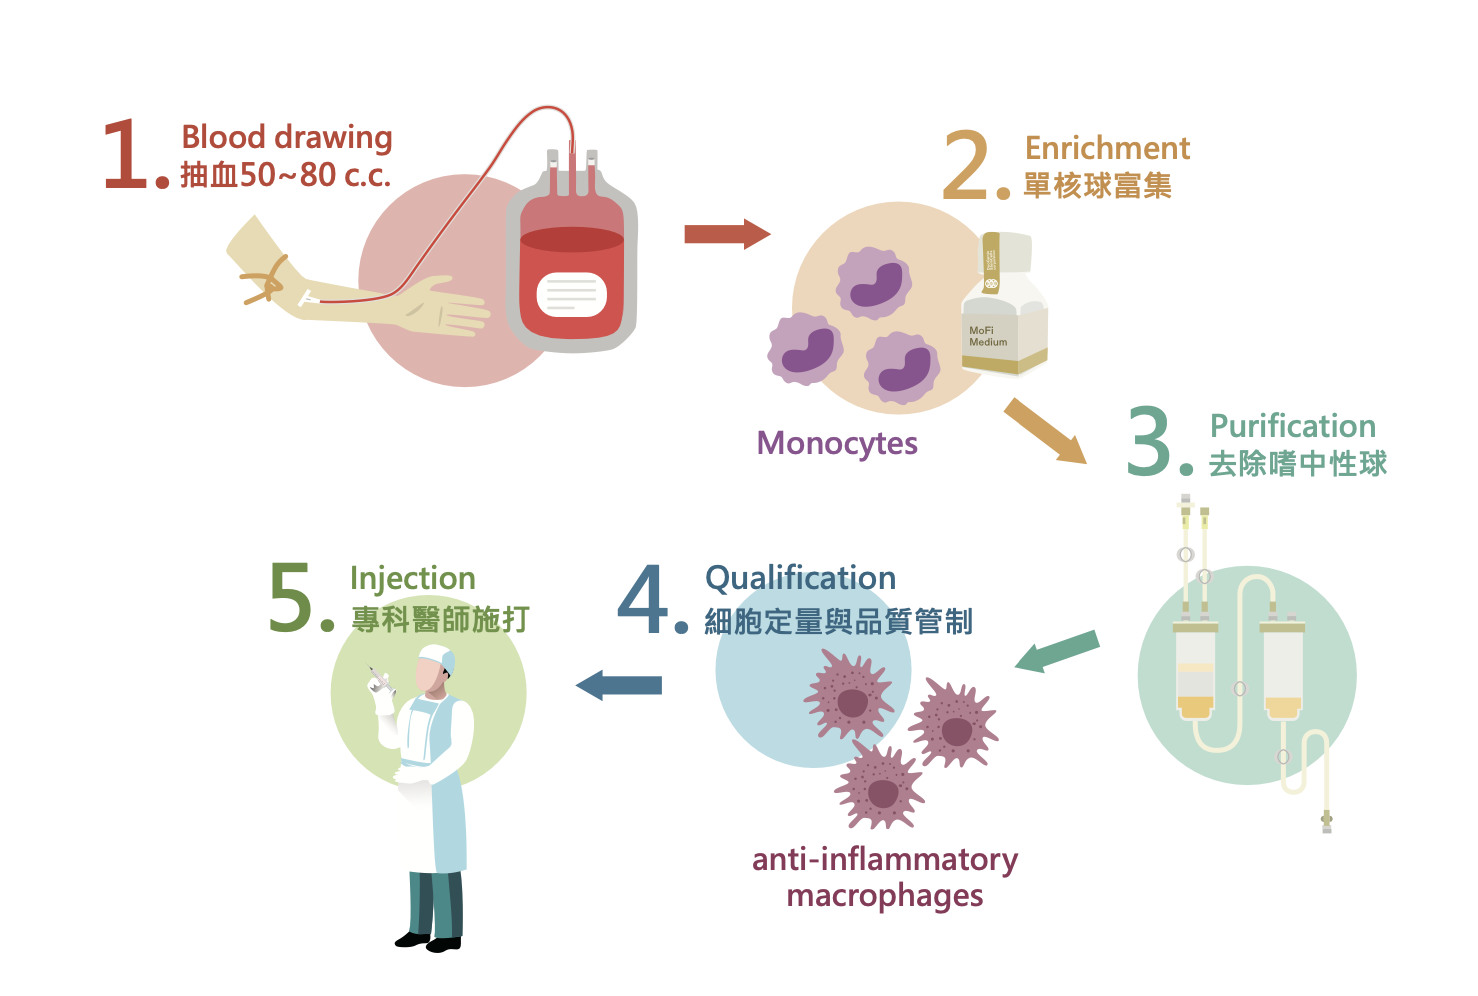

治療前後注意事項與適用範圍

治療前建議經醫師臨床說明或參閱衛教內容後,維持充足睡眠、多補充水分、避免身體疲勞,飲食以清淡為主並避免飲酒。治療後若注射部位有腫脹感,多屬正常現象;門診當日治療後一般可返家,依正常作息生活。若有傷口紅腫熱痛、身體發燒等異常情況,請立即回診就醫,並於治療後七天內避免高溫熱水澡、浸泡溫泉及劇烈運動。

圖片中同時整理了常見適用範圍,包括網球肘、旋轉環帶肌腱炎、下背痛、髖關節炎、退化性關節炎與足底筋膜炎等;另外亦提醒,腫瘤患者、自體血液疾病患者、嚴重貧血患者與凝血功能異常患者,通常不適用此療法,實際仍須由醫師審慎評估。

不適用族群與療程提醒

依目前衛教資料整理,腫瘤病患或曾有腫瘤病史者、自體免疫疾病患者、嚴重貧血患者、血液疾病患者及凝血功能異常者,皆需由醫師審慎評估,部分情況下通常不建議施作。實際是否適合療程,仍須由門診醫師依個人身體狀況、病史與影像檢查完整判斷。

療程前請務必配合醫師說明,主動告知慢性病史、特殊藥物使用情況與既往治療經驗;療程後如有明顯紅腫熱痛、發燒或其他異常不適,應立即回診就醫。